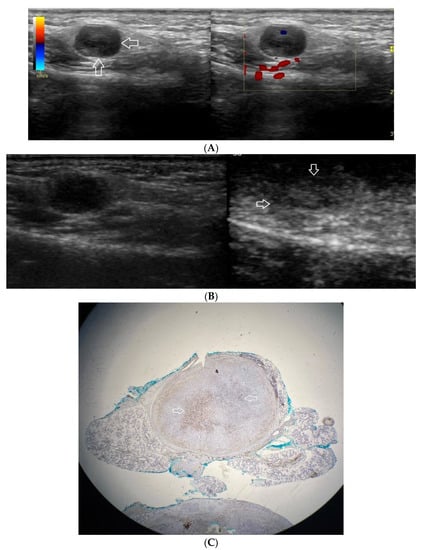

Figure 4.

(A−C) Warthin’s tumour. (A) Routine ultrasonographic examination in B presentation and colour Doppler: a big hypoechogenic well-demarcated focal lesion of a heterogeneous echostructure (white arrows). On CD, a low blood flow is observed. (B) Contrast-enhanced imaging in arterial phase: a strong homogeneous enhancement of a peripheral part of the lesion (white arrows). In the central part of the tumour, irregular areas without enhancement. (C) Pathomorphological image, H & E stain. Large areas of irregular shape containing fluid (white stars). A part containing glandular tissue located peripherally.